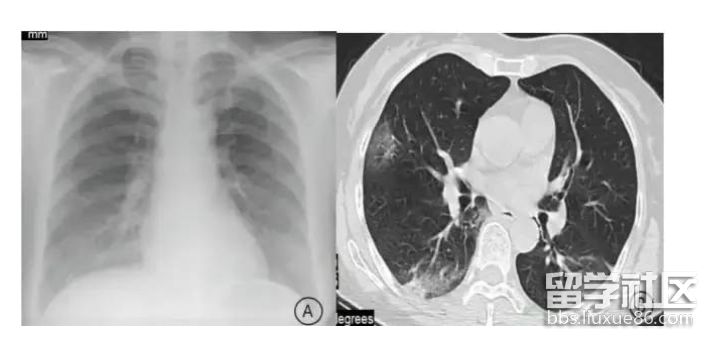

在呼吸科医生看来,流感致死的一个重要原因就是,它侵蚀肺部导致重度肺炎从而让患者缺氧而死。所以,这也是此次甲流患者中出现“白肺”的原因。

目前已有的病例统计中,老年人、儿童、孕妇和有基础疾病的人群均是“白肺”的高发人群。